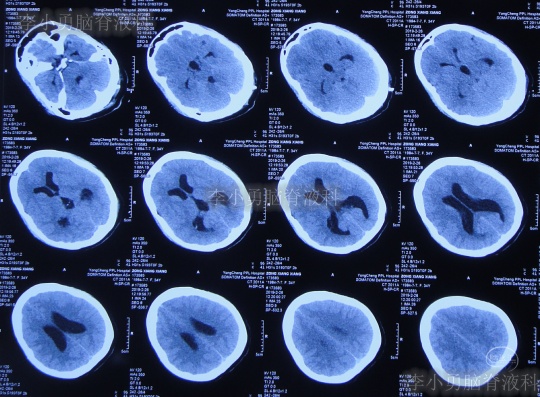

患者2019年2月初,因数次出现发作性黑蒙,2019年2月10日就诊于当地的河南省永城市某医院,查头颅CT未见明显异常(图-1);次日再查头颅核磁、颈椎核磁(图-2、图-3)后发现小脑扁桃体下疝畸形合并脊髓空洞。

图-1:2019年2月10日头颅CT